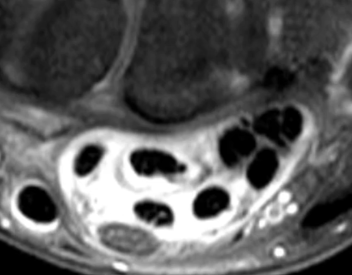

Ténosynovite du Tunnel Carpien